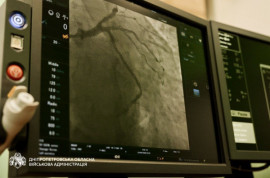

Стентування застосовують при ішемічній хворобі серця, коли медикаментозне лікування не дає результату або виявлено значне звуження коронарних артерій. Операція дозволяє відновити кровотік і знизити ризик інфаркту.